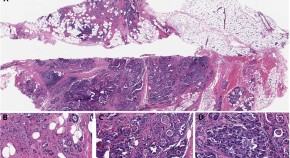

Renal manifestations in Crohn's disease—a chronic relapsing inflammatory disease characterized by mucosal ulcerations of the digestive tract—are rare. Tubulointerstitial nephritis has been reported in Crohn's disease, but most cases have occurred in patients treated with 5-aminosalicylic acid derivatives, which are known to be nephrotoxic. In this Case Study, Waters et al. present two cases of tubulointerstitial nephritis occurring in patients with Crohn's disease, and emphasize that physicians should be aware of this serious and under-recognized complication.